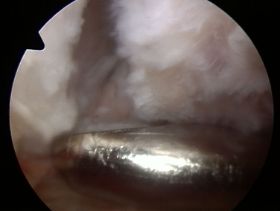

staw AC podczas artroskopii : bez zmian przestrzeni stawowej